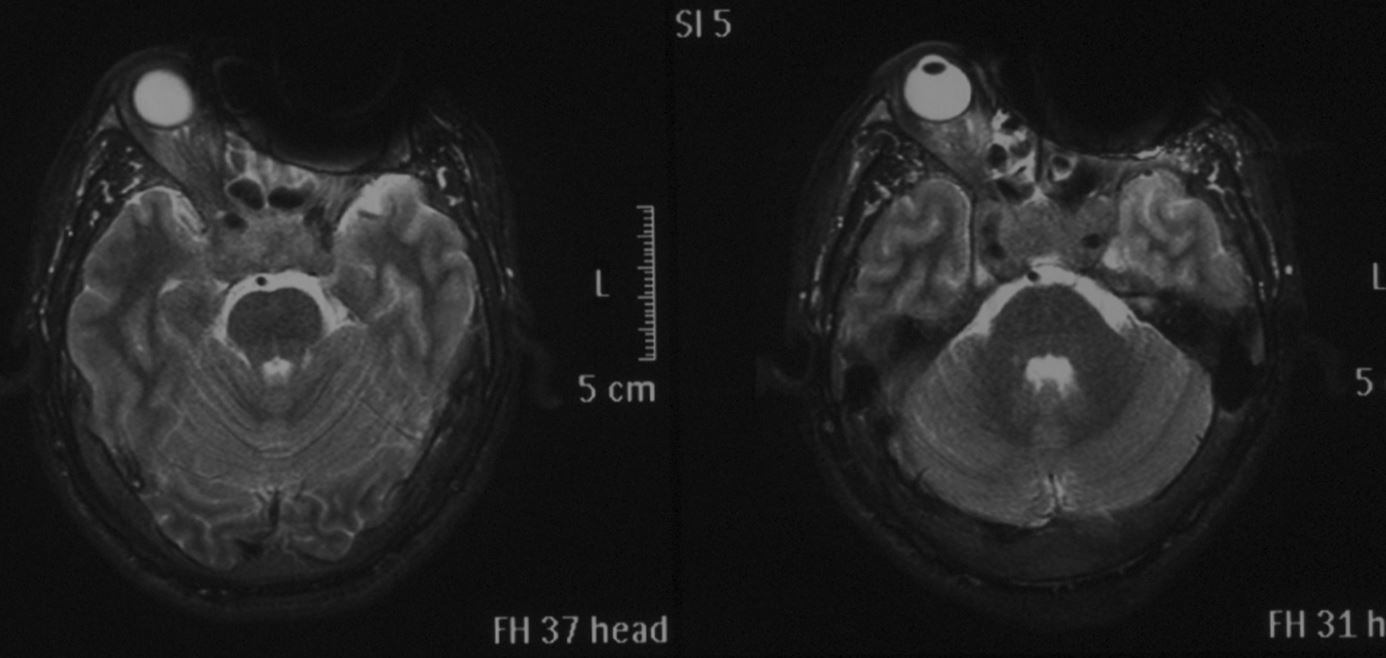

头颅MRI示:鞍区占位性病变,肿瘤大小约2*2.8cm,T1等信号,T2混杂信号,增强后部分强化。肿瘤刚突破鞍底向蝶窦生长,向上突破鞍隔向上生长,视交叉明显受压,左侧较为严重。肿瘤向两侧生长,海绵窦及颈内动脉受侵犯。垂体瘤卒中可能大。

术中见灰白色肿瘤组织,局部可见暗褐色陈旧性出血,肿瘤全切,鞍隔明显塌陷,无脑脊液漏。